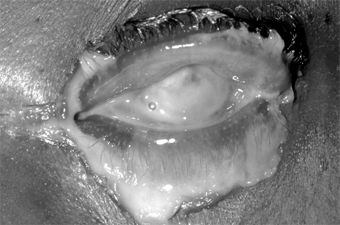

Complications & Sequelae

Conjunctival scarring is a frequent complication of trachoma and can destroy the ductules of the accessory lacrimal glands and obliterate the orifices of the lacrimal gland. These effects may drastically reduce the aqueous component of the precorneal tear film, and the film's mucous components may be reduced by loss of goblet cells. The scars may also cause distortion of the upper lid with inward deviation of individual lashes (trichiasis) or of the whole lid margin (entropion), so that the lashes constantly abrade the cornea. This often leads to corneal ulceration, bacterial corneal infections, and corneal scarring (Figure 5-2).

Figure 5-2

Figure 5-2: Advanced trachoma following corneal ulceration and scarring. Note the fly on the temporal aspect of the lower lid. The fly is a principal vector for trachoma.